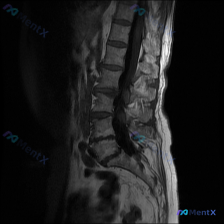

- 关注点是“脊柱侧弯”,但只提供了腰椎MRI T2序列矢状位图像

- 矢状位里能看到的是:腰椎生理前凸变直,多节段椎间盘T2信号普遍减低(L4/5、L5/S1尤其明显),L4/5、L5/S1椎间盘有突出/膨出,后缘轮廓不平整,高度也有变窄

- 另外还能看到硬膜囊在这两个节段受压,脑脊液高信号间隙变窄/消失,中央椎管前后径变窄,后方黄韧带区域有T2低信号增宽

- 椎体骨髓信号没看到明显弥漫性异常T2高信号,部分椎体终板区域T2信号轻度减低